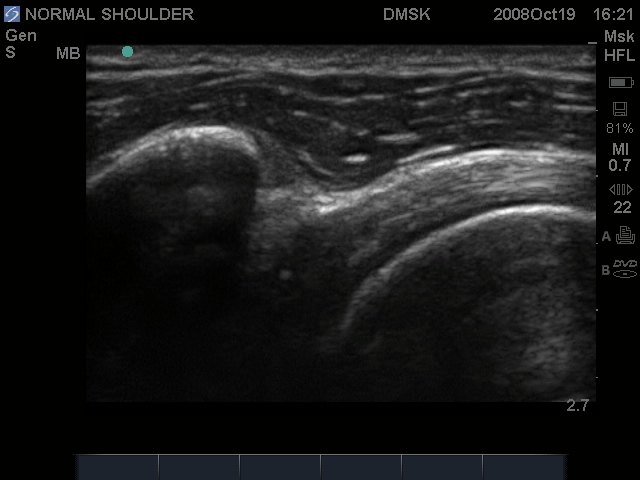

Biceps Tendon Transverse, at the level of the Lesser Tuberocity